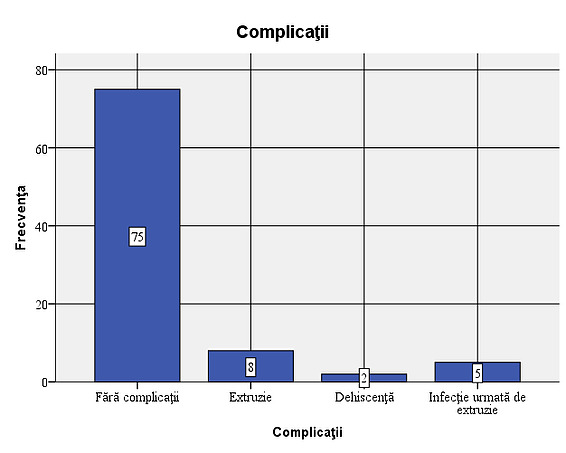

Figure 2: Types of implants used in the sample In 15 of the patients studied (16.7%), complications were observed: 5 cases of infections, 13 cases with extrusions and 2 cases with dehiscence. Out of the total of 15 cases with complications, extrusion occurred in 86.7%. Considering that all cases of infection were followed by extrusion, the situation of complications that occurred is as follows: 8 cases (8.9% of the total number of patients studied) with extrusion only, 5 cases (5.6%) of infection followed by extrusion and 2 cases (2.2%) with dehiscence. In most of the cases with complications, the association of infection with extrusion occurs, dehiscence not being associated with extrusion or infection.

Figure 3: Frequency of complications – 8 cases (8.9% of the total patients studied) with extrusion only, 5 cases (5.6%) of infection followed by extrusion and 2 cases (2.2%) with dehiscence.

- In 15 of the patients studied (16.7%) complications were observed: 5 cases of infections, 13 cases of extrusions and 2 cases of dehiscence. Considering that all cases of infection were followed by extrusion, the situation of complications that occurred is as follows: 8 cases (8.9% of the total number of patients studied) with extrusion only, 5 cases (5.6%) of infection followed by extrusion and 2 cases (2.2%) with dehiscence;